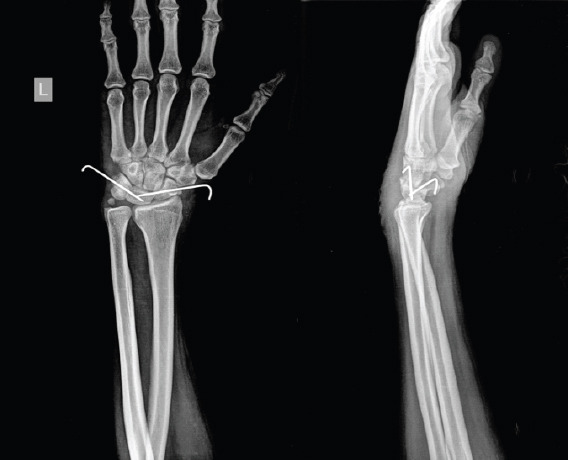

Case report: We present a case of a 40-year-old polytrauma patient who sustained multiple injuries following a road traffic accident. His acute injuries were predominantly treated, while a neglected isolated lunate dislocation remained undiagnosed. Three weeks later, the patient presented with acute carpal tunnel symptoms - severe wrist pain, numbness, and weakness in the distribution of the median nerve.Physical examination demonstrated tenderness over the volar wrist, reduced range of motion, and a positively elicited Phalen's and Tinel's sign. Radiographs and nerve conduction studies confirmed a neglected volar lunate dislocation causing compression of the carpal tunnel. Surgical intervention was performed through a combined dorsal and volar approach. Open reduction and internal fixation were followed by decompressive carpal tunnel release.Postoperatively, the patient recovered well, with resolution of symptoms and return of nearly normal wrist motion and grip strength at 1-year follow-up.

Conclusion: This case underscores the importance of evaluating peripheral joints in polytrauma and shows that even delayed lunate dislocations presenting with carpal tunnel syndrome can be successfully treated using a dual approach without any salvage procedure up to 3 months.